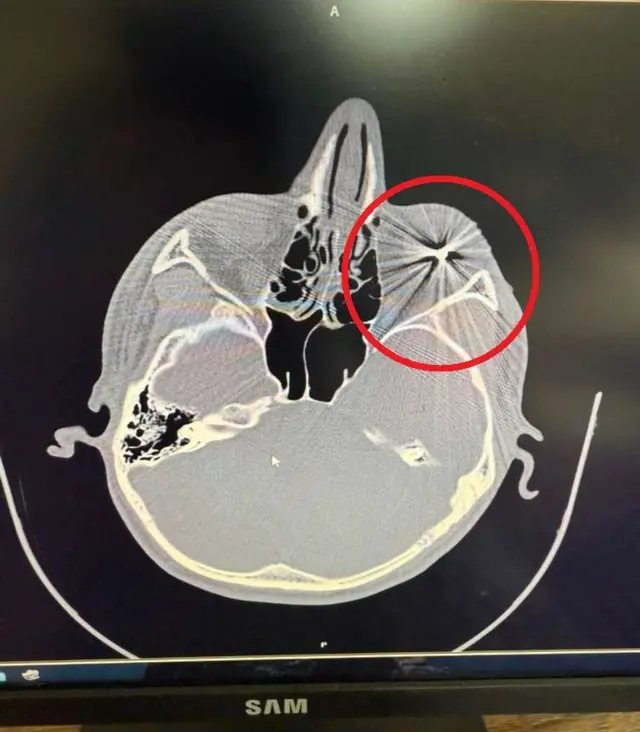

بخش راستیآزمایی بیبیسی به تصاویر و مدارک پزشکی چند معترض را که در اعتراضات اخیر در مشهد بر اثر گلوله ساچمهای از ناحیه چشم آسیب دیده بودند، دستیافته است.

تصویر سیتیاسکن یکی از معترضان فرو رفتن گلوله ساچمهای در بافت چشم را بهوضوح نشان میدهد. بیبیسی برای حفظ امنیت این افراد، از ذکر اسم آنها خودداری میکند.